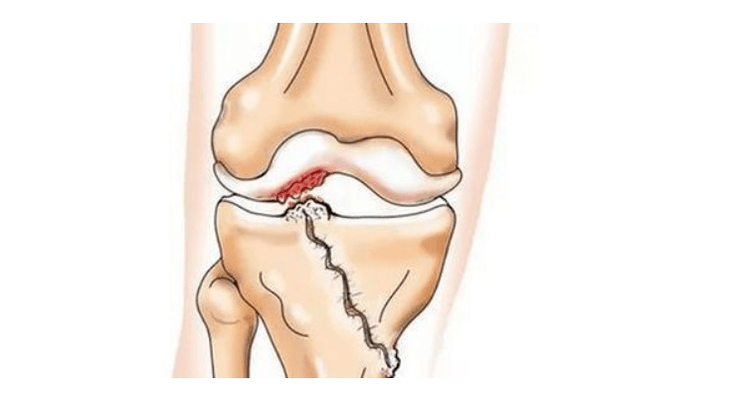

• injuries (fractures, tears of the meniscus and anterior cruciate ligaments).Unfortunately, these injuries put excessive stress on the cartilage in everyone, regardless of age.The fracture of any part of the bones covered with cartilage is accompanied by the formation of an unevenness - a "step".In this area, when moving, erosion occurs and arthrosis occurs;

crack in the knee joint

With arthrosis (osteoarthrosis), along with progressive destruction of cartilage, loss of elasticity and shock absorption properties, bones are gradually involved in the process.Under load, sharp edges (exostoses) appear, which are mistakenly considered "salt deposits" - salt deposition does not occur with classic arthrosis.As arthrosis progresses, it continues to "eat" the cartilage.Then the bone is deformed, cysts are formed there, all the structures of the joint are affected, the leg bends.